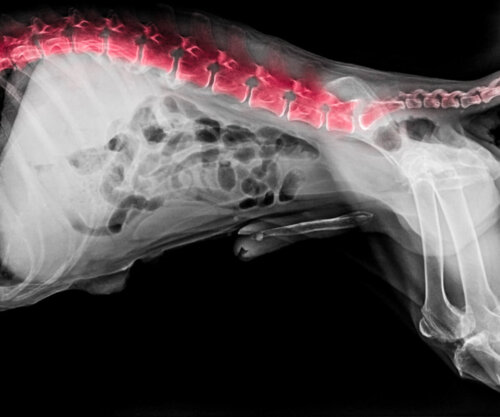

9. Zespół wobblera u psów rasy bernardyn

Jest to kolejna choroba często występująca u bernardynów. Jest to dolegliwość, która ma swoje źródło w odcinku szyjnym. Konkretnie jest to problem kręgów szyjnych i krążków międzykręgowych, który powoduje ucisk rdzenia kręgowego. Prowadzi to do problemów neurologicznych.

W rzeczywistości jego nazwa (Wobbler) jest używana do określenia chwiejnego chodu, który pojawia się u psa, gdy cierpi na ten syndrom, ponieważ wobble to w języku angielskim “zataczać się”. Oprócz zataczania się, inne objawy choroby obejmują sztywność karku, zmęczenie, osłabienie, obrzęk kończyn, częściowy lub całkowity paraliż lub trudności ze wstawaniem i poruszaniem się.